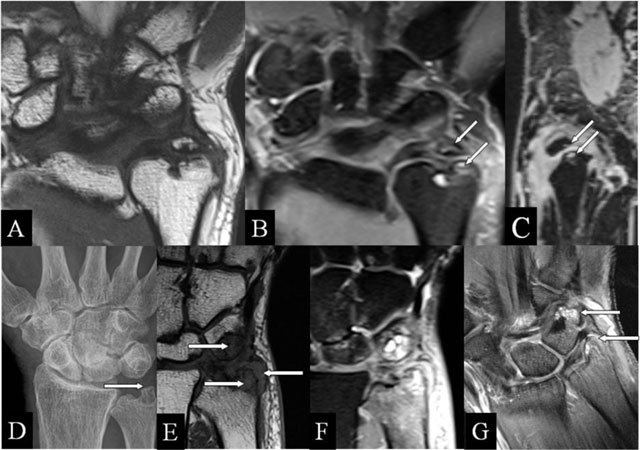

Figure 3

Ulnar (intra)styloid and stylotriquetral abutment. (A, E) Coronal SE T1-WI; (B, F) Coronal SE PD-WI FS; (C) Sagittal 3D-GRE; (D) PA plain radiograph; and (G) Coronal SE T1-WI FS with gadolinium. (A–C) Neoarticulation in the center of the ulnar styloid process, surrounding marrow oedema, (B) and juxta-articular cysts (arrows) (B, C). (D–F) Stylotriquetral abutment with flattening of the tip of the styloid process (D), bone marrow oedema and synovitis (E, F), and contrast enhancement of the marrow oedema and the synovitis (G).